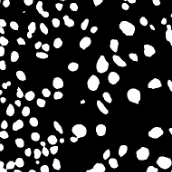

In practice, directly using point annotation for the nuclei segmentation could suffer from the data-imbalance problem due to insufficient supervision information. To alleviate this issue, we adopt the Voronoi diagram [24] and the -means clustering method [25] to generate Voronoi label and cluster label, respectively. Specifically, for Voronoi labels, as shown in Fig. 1, the image is divided into convex polygons based on the point annotations with the assumptions that the point labels are at the nuclei centers and nuclear shapes are convex (even though these assumptions are not necessarily valid). For cluster labels, as shown in Fig. 1, we utilize the -means to obtain more supervision information of nuclei boundary and shape as follows. First, we calculate the distance maps from the point labels by performing distance transform between each pair of points. Second, the distance maps are combined with the original H&E stained images to conduct the -means clustering to divide all pixels into clusters: nuclei, background, and ignored area. The clusters that have maximum and minimum overlap with the point annotations are labeled as nuclei and background, respectively. The remaining one is the ignored class. The introduction of an ignored area allows pixels that cannot be easily determined as nuclei or background with certainty not be forced into either class, ensuring that the clustering can assign correct pixel labels as much as possible [27]. Third, several morphological operations are adopted to refine the cluster label, including connected domain labeling, scattered region removing, morphological opening operation, and binary hole filling.

where and denote the Voronoi label and cluster label of nuclei at the -th pixel, respectively; denotes the prediction of the segmentation network with H-component as input; and (i.e., or ) is the set of non-ignored pixels. As illustrated in Fig. 1, the Voronoi label is used to supervise the network to separate overlapping nuclei, while the cluster label could provide coarse shape and boundary information for nuclei segmentation. In the following, we elaborate the co-training strategy to further provide supervision to the ignored area of the coarse cluster labels, denoted with the blue color in Fig. 1.

where is the -th pixel of the pseudo label, is the set of all pixels, and denotes the predictions of with respect to the H-component . With the training set split into two non-overlapping subsets and , two segmentation networks are trained with the coarse labels (i.e., the Voronoi and cluster labels) by and , respectively, the two networks could transfer knowledge to each other with their respective pseudo labels, so as to compensate for the missing supervision information. However, the segmentation performance may still suffer from the inaccurate cluster label, as shown in Fig. 1. Hence, our next step is to explore an auxiliary colorization task that transforms H-component images back into the original H&E stained images from which more precise nuclei boundaries can be obtained.

To investigate the impact of the proposed co-training and colorization methods, we validate the effectiveness of each module on the MoNuSeg dataset. Considering that Voronoi labels provide more shape supervision information than point annotation, we regard the model that jointly uses the point annotation and the Voronoi label as the baseline, and mainly evaluate the improvement of each module upon this baseline in Table III. Model A utilizes only point annotation and Voronoi labels with cross-entropy loss. For a fair comparison with co-training, we employ two separate models which have the same architectures for co-training and average the predictions of the two models in inference. Model B further adopts the cluster label. It can be seen that the cluster loss is beneficial in segmenting overlapping nuclei, improving the from 60.20% to 72.48% and the AJI from 43.01% to 51.77%, which indicates that simply using the point annotation and the derived Voronoi labels cannot provide sufficient supervision for the nuclei segmentation due to the lack of boundary and area information. However, the cluster labels generated by the -means algorithm cannot separate close nuclei which would introduce distraction to the training process, as shown in Fig. 1. To address this challenge, Model C utilizes the co-training strategy that the two models facilitate each other in a bootstrapping way to eliminate the distraction brought by the cluster labels. As expected, co-training brings a consistent improvement in all metrics, including an 1.19% increase to AJI. We believe that co-training compensates for the loss of supervision information in the uncertain regions in the cluster label, and the probability map with EMA by another model provides more precise and robust supervision in the nuclei boundary. Visualization of the segmentation results can be found in Fig. 3, and it can be seen that with the co-training strategy, the model can achieve more accurate results, especially in the nuclei boundary area. Model D involves colorization as a proxy task to implicitly learn to be self-aware of the nuclei boundary. Instead of directly coloring the H-component (Fig. 4(a)) to the H&E map (Fig. 4(d)), we use the segmentation probability map (Fig. 4(b)) as the input of the colorization network, which can help us to boost the segmentation accuracy. The experimental result shows that integrating the colorization tasks could not only improve the by 1.54% and AJI by 3.24%, but also promote Acc by 0.18% without dropping F1 score, proving that the colorization task has a significant guiding effect on nuclei segmentation. In Fig. 4(c), the improvement of colorization in the nuclei boundary area can also be observed. In general, the four modules used in our method have complementary advantages. By minimizing the weighted sum of the four losses, the proposed framework can distinguish between nuclear and non-nuclear to the greatest extent.